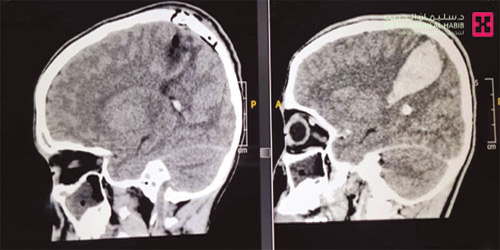

ذكر ذلك د. ناجي مسعود استشاري جراحة المخ والأعصاب بالمستشفى. وأضاف أن الطفل راجع مستشفى آخر بعدما شعر بشكل مفاجئ بألم حاد في الرأس، والغثيان والاستفراغ، قبل أن يتطور الأمر ويصاب بشلل تام في النصف الأيمن من الجسم، بالإضافة إلى أنه بدأ يفقد الوعي تدريجياً. وقد تمت إحالة الطفل إلى مستشفى الدكتور سليمان الحبيب، حيث أُدخل العناية المركزة مباشرة ووضع على التنفس الصناعي. وقد أوضحت الفحوصات وجود نزيف حاد بالفص الأيسر من الدماغ في منطقة الحركة، وكذلك وجود تشوه في الأوردة والشرايين وبناءً على ذلك أُجريت عملية للطفل استمرت «5» ساعات تم خلالها إزالة النزيف بالكامل وإغلاق وإزالة التشوّه في الأوردة والشرايين.

وقد تحسنت المؤشرات الحيوية للمريض وتم تحويله للعناية المركزة للأطفال حتى استقرت حالته، وبعدها نقل إلى غرفة التنويم وبقي تحت المراقبة والرعاية الحثيثة لمدة «7» أيام تحسنت خلالها حالته الصحية بنسق سريع، إذ استطاع تحريك يده ورجله اليمنى وغادر المستشفى مشياً على قدميه.